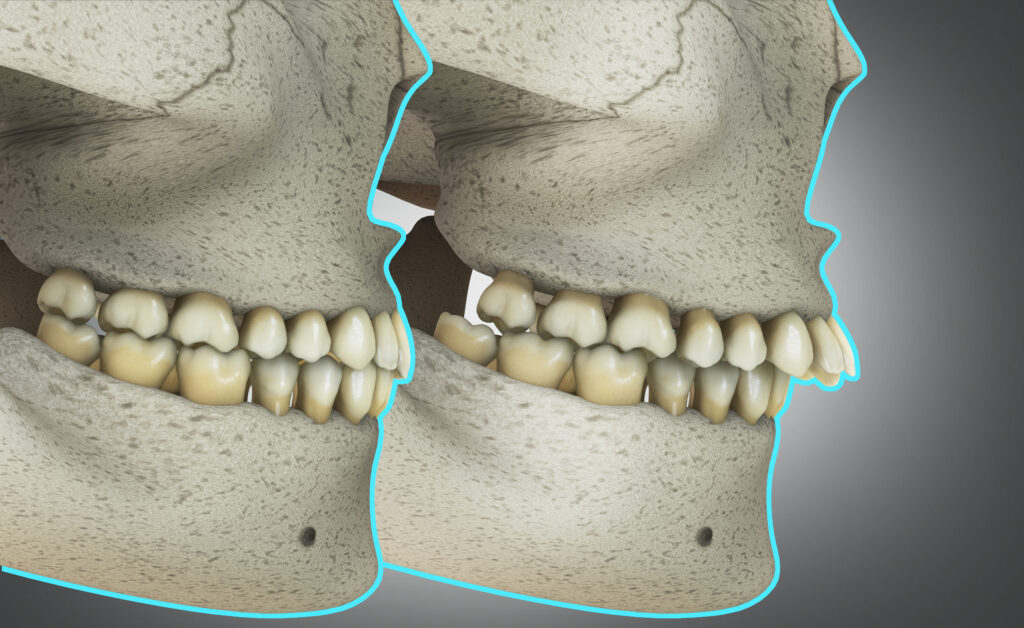

Orthognathic surgery in Krakow – surgical correction of malocclusion

Orthognathic surgery helps to solve problems with the bite that cannot be treated with braces or aligners. If you have…

Learn more

• Correction of bite and jaw anomalies, and deformations resulting from congenital defects, tumors, or severe dental trauma treatment.